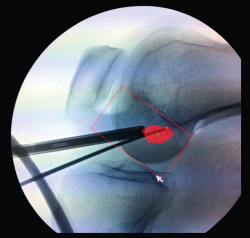

Aunque el punto de entrada extraarticular pueda variar, la salida del túnel tibial a nivel intraarticular es fija. Idealmente, esta será sobre el muñón residual del LCA, centrado sobre la espina tibial interna, paralelo al borde posterior del cuerno anterior del menisco externo y 7 mm anterior al ligamento cruzado posterior (LCP) (Figura 14). Jugando con el ángulo de la guía tibial podremos variar la longitud del túnel. El objetivo es permitir que las fibras de la plastia se dispongan de forma inclinada y paralelas a la línea de Blumensaat en extensión (Figura 15).

Figura 14. Aguja guía en la huella tibial del ligamento cruzado anterior.